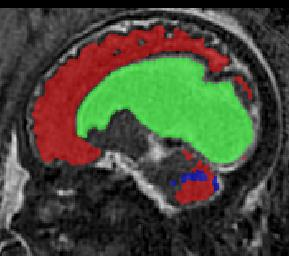

Limiting failures of machine learning systems is of paramount importance for safety-critical applications. In order to improve the robustness of machine learning systems, Distributionally Robust Optimization (DRO) has been proposed as a generalization of Empirical Risk Minimization (ERM). However, its use in deep learning has been severely restricted due to the relative inefficiency of the optimizers available for DRO in comparison to the wide-spread variants of Stochastic Gradient Descent (SGD) optimizers for ERM. We propose SGD with hardness weighted sampling, a principled and efficient optimization method for DRO in machine learning that is particularly suited in the context of deep learning. Similar to a hard example mining strategy in practice, the proposed algorithm is straightforward to implement and computationally as efficient as SGD-based optimizers used for deep learning, requiring minimal overhead computation. In contrast to typical ad hoc hard mining approaches, we prove the convergence of our DRO algorithm for over-parameterized deep learning networks with ReLU activation and a finite number of layers and parameters. Our experiments on fetal brain 3D MRI segmentation and brain tumor segmentation in MRI demonstrate the feasibility and the usefulness of our approach. Using our hardness weighted sampling for training a state-of-the-art deep learning pipeline leads to improved robustness to anatomical variabilities in automatic fetal brain 3D MRI segmentation using deep learning and to improved robustness to the image protocol variations in brain tumor segmentation. Our code is available at https://github.com/LucasFidon/HardnessWeightedSampler.